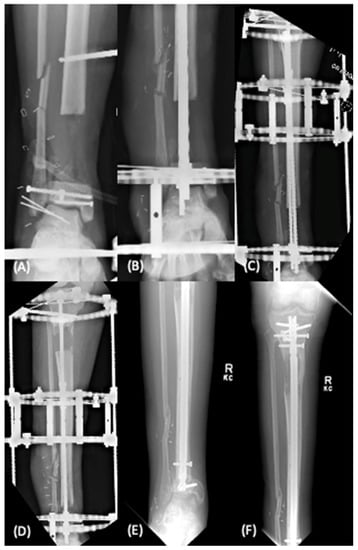

Figure 2.

Distraction osteogenesis for the management of distal tibial metadiaphyseal defect (arrow). Initially treated with debridement and temporary hybrid fixation (A). Subsequently underwent first stage procedure involving intramedullary nail and ringed external fixator placement and proximal tibia corticotomy (B,C). Midpoint follow up demonstrates proximal to distal transport (D). After completion of transport, subsequent docking, and removal of ringed external fixator with proximal deposition of bone (E,F).